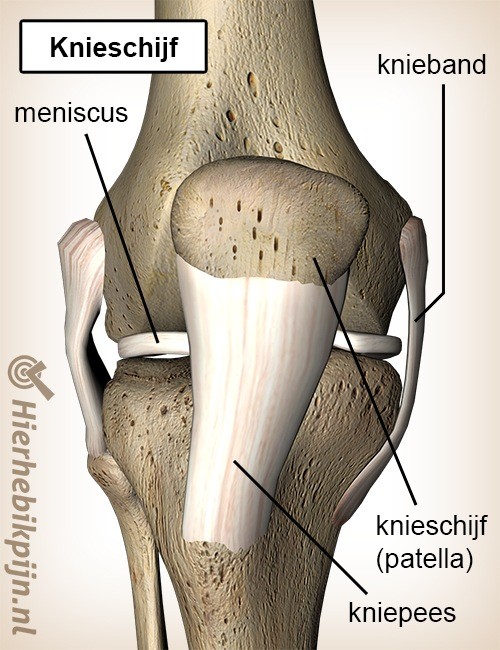

- page_id_307_title

page_id_307_title

page_id_307_lead

page_id_307_body